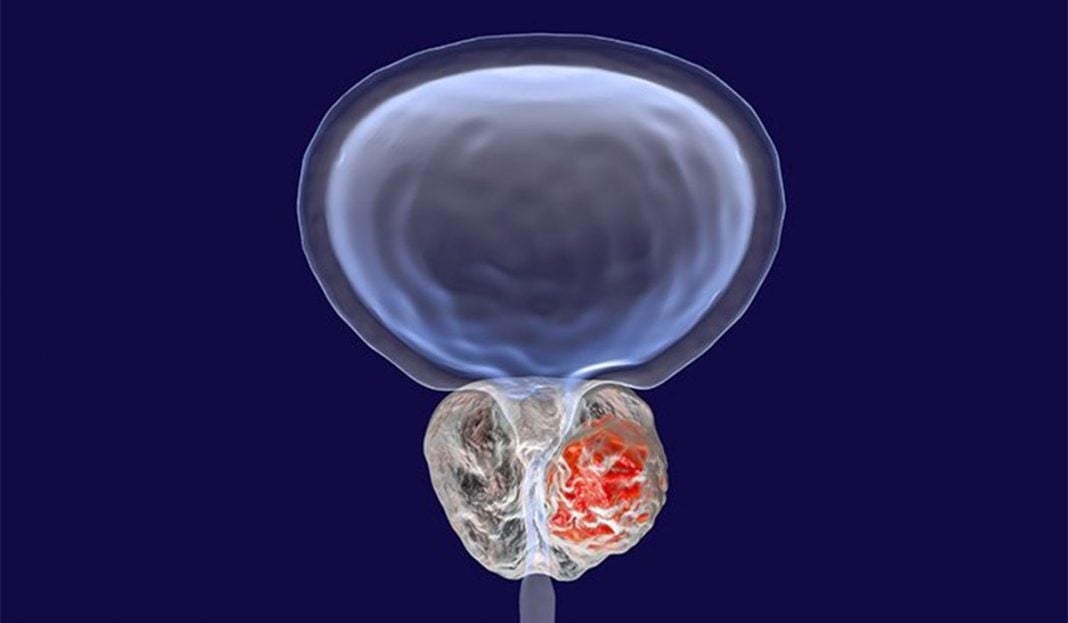

HoLEP: Mια πραγματική επανάσταση στην Ουρολογία μετά από 5 δεκαετίες.

Η HoLEP έχει εισαχθεί στο Τμήμα των ιατρών ως επέμβασις εκλογής για την θεραπεία αδένων ανεξαρτήτως μεγέθους έως και 200cc, καθώς η ομάδα διαθέτει από τα πρώτα Low Power Holmium Lasers στην Αθήνα, έχοντας αντιμετωπίσει δεκάδες ασθενείς με επιτυχία.

Όπως μας ενημερώνει ο Χειρουργός Ουρολόγος N. Μπαφαλούκας, η χαμηλή ενέργεια και συχνότητα του Laser προσαρμόζεται στην ανατομία του κάθε ανδρός ξεχωριστά και επιτυγχάνει πλήρη εκπυρήνιση του αδένος και εντελώς αναίμακτα, απωθώντας ευγενικά τον ιστό όπως ακριβώς αφαιρείται το εσωτερικό ενός πορτοκαλιού από την κάψα του, γεγονός αδύνατον για τις παλαιές τεχνικές και καθιστώντας μηδενική την πιθανότητα επιπλοκών και επανεπεμβάσεων.

- Διατηρείται ο ιστός για βιοψία και διάγνωση επειδή ακριβώς δεν απανθρακώνεται.

- Διατηρείται η στύσις και δίδεται ειδική μνεία στην διατήρηση των εκσπερματιστικών πόρων.